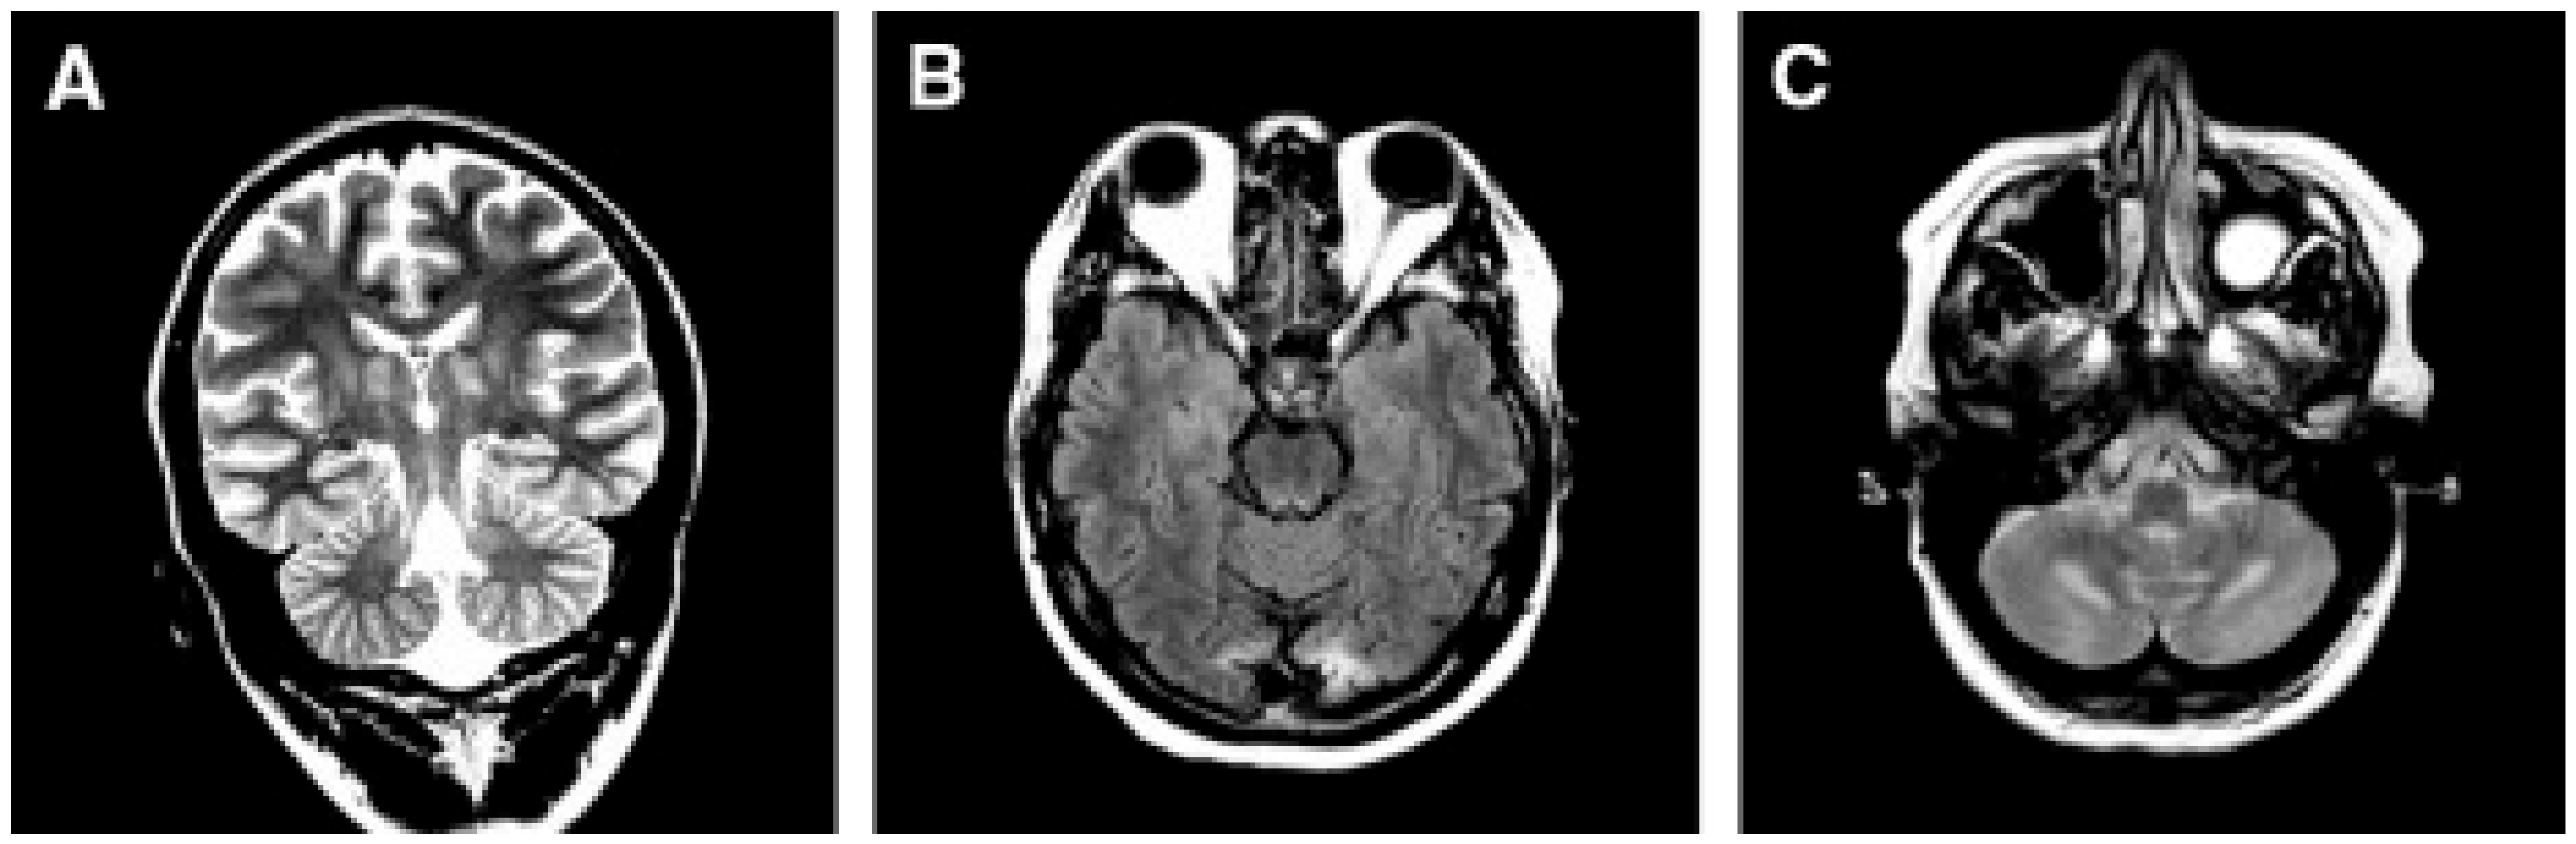

- Barkovich, A.J.; Good, W.V.; Koch, T.K.; Berg, B.O. Mitochondrial Disorders: Analysis of Their Clinical and Imaging Characteristics. AJNR Am. J. Neuroradiol. 1993, 14, 1119–1137. [Google Scholar] [PubMed]

- Oldfors, A.; Fyhr, I.M.; Holme, E.; Larsson, N.G.; Tulinius, M. Neuropathology in Kearns-Sayre Syndrome. Acta Neuropathol. 1990, 80, 541–546. [Google Scholar] [CrossRef]

- McKelvie, P.A.; Morley, J.B.; Byrne, E.; Marzuki, S. Mitochondrial Encephalomyopathies: A Correlation between Neuropathological Findings and Defects in Mitochondrial DNA. J. Neurol. Sci. 1991, 102, 51–60. [Google Scholar] [CrossRef]

- Tanji, K.; Vu, T.H.; Schon, E.A.; DiMauro, S.; Bonilla, E. Kearns-Sayre Syndrome: Unusual Pattern of Expression of Subunits of the Respiratory Chain in the Cerebellar System. Ann. Neurol. 1999, 45, 377–383. [Google Scholar] [CrossRef]